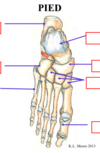

Identifiez